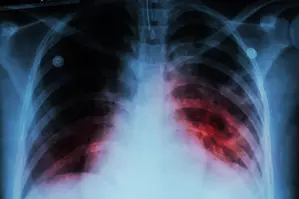

New Delhi, Dec 3 The Centre on Tuesday stated that about 21.69 lakh tuberculosis (TB) cases have been notified between January and October 2024.

“Notified TB cases increased from 18.05 lakh in 2020 to 25.52 lakh in 2023,” said Union Minister of State for Health and Family Welfare, Anupriya Patel, in a written reply in the Rajya Sabha.

“About 21.69 lakh TB cases have been notified between January and October in 2024,” she added.

“The incidence rate of TB in India has shown a 17.7 per cent decline from 237 per 100,000 population in 2015 to 195 per 100,000 population in 2023. TB deaths have reduced by 21.4 per cent from 28 per lakh population in 2015 to 22 per lakh population in 2023,” Patel said.